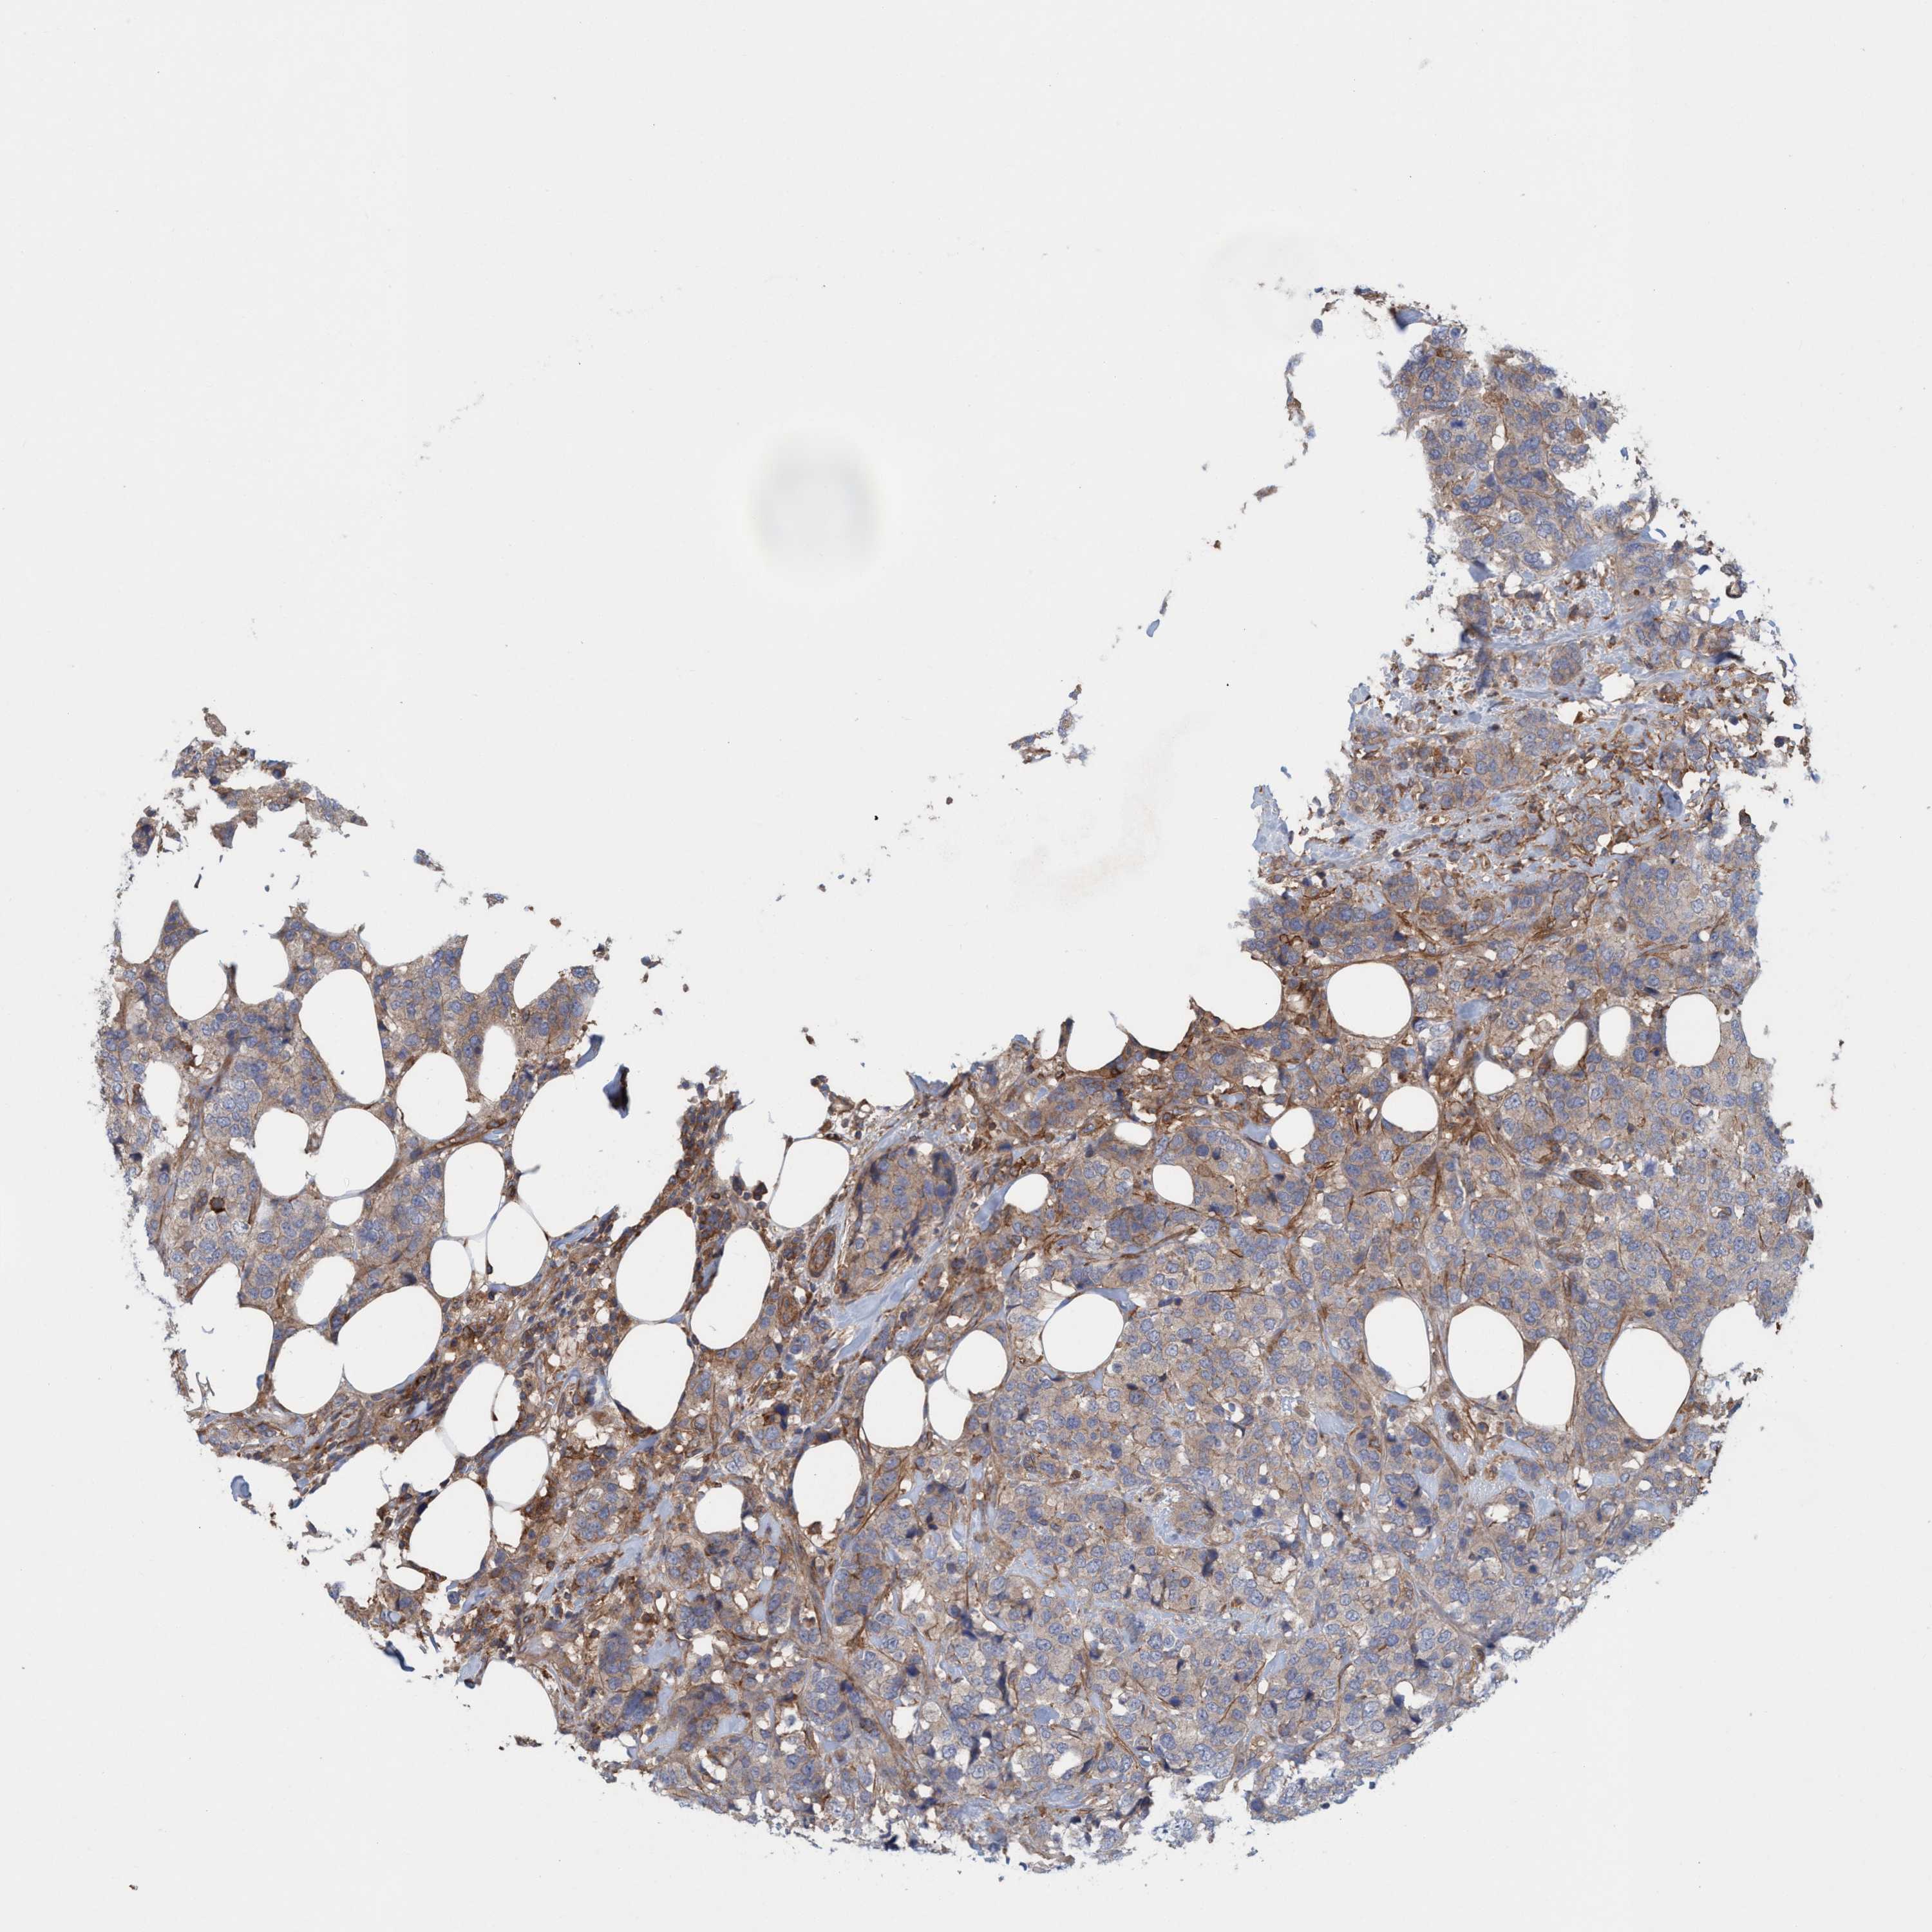

BRCA TCGA BRCA VALIDATION PROTEIN EXPRESSION

ANTIBODIES

AND

VALIDATION